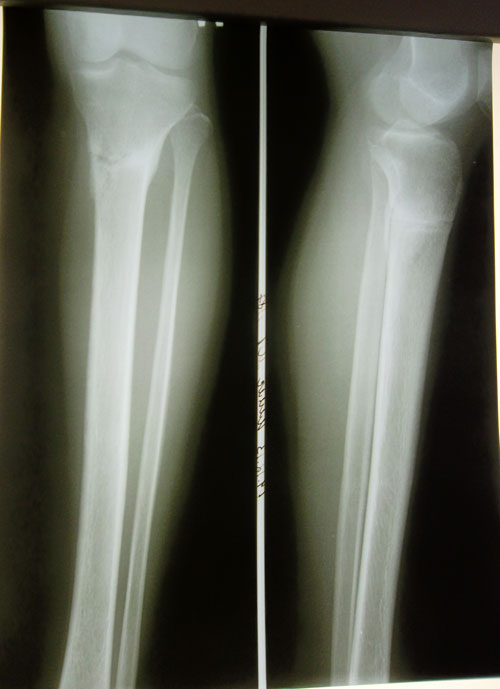

Дата операции 03.07.2013г.

Дата снятия аппаратов 15.10.2013г.

Срок лечения 103 дня.

Рентген в 2 месяца после снятия аппаратов.

Рекомендовано: ещё месяц воздержаться от ношения каблуков. Через месяц начните с 5-6 см, постепенно по нарастающей (я про каблучки). Можете посещать занятия боди балетом для растяжки и красивой осанки и походки(это можно делать в домашних условиях по интернету). Ждём фото ножек на каблучках! Не забывайте про форум!